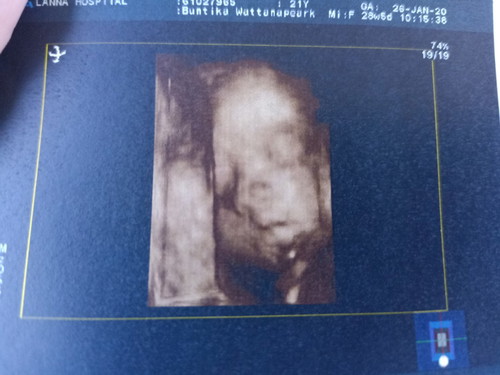

เป็นแม่เลี้ยงเดี่ยวค่ะ โดนพ่อของเด็กทิ้ง เพียงเพราะ เค้าไม่อยากลำบากต้องมานั่งรับผิดชอบเรากับลูก ตั้งแต่รู้ว่าท้อง พ่อแม่ฝ่ายชาย ไม่เคยช่วยเหลืออะไรเลยค่ะ มีแต่ ฝั่งเรา ที่ออกค่ารักษา เขาไม่ช่วยเรื่องเงิน ยังไม่เจ็บใจเท่า เขาก้อเป็นแม่คน ที่ต้องแยกทางกับสามีเลี้ยงลูกคนเดียวมาก่อน แต่เขากับ เข้าข้างลูกตัวเอง ที่จะเลิกกับเรา และขอ ไม่รับผิดชอบเด็ก เลยแม้แต่น้อย เราเจ็บใจมาก ที่ ครอบครัว ฝ่ายชายทำกับเราและลูกเราขนาดนี้ แต่วันนี้ รู้แล้วว่า ใครทำกรรมใดไว้ กรรมนั้นย่อมส่งผลของมันเสมอ และของขวัญที่ดีที่สุด คือลูกชายที่น่ารักมากๆ นี้แหละค่ะ ความโชคดี ที่ไม่ต้องทน กับผู้ชาย เห็นแก่ตัว มักมาก อยากได้อยากมี จนลืม นึกถึง เด็กว่าเค้าจะเป็นยังไง และก้อโชคดีมากๆ ที่ลูกแข็งแรงมาก และ ครบ 32 เป็นแม่คนแล้ว เราจะท้อไม่ได้ ??

บ้านนี้ก็เช่นกัน เลิกกับพ่อของลูกไปตั้งแต่อุ้มท้อง 4เดือน ตอนนี้7เดือนแล้ว ชีวิตหลังจากความเสียใจ มีความสุขมากเลยค่ะ ทำให้รู้ว่าต้องอยู่เพื่อใคร ลูกคือของขวัญที่มีค่ามาก ตัด1คนเลวๆออกไปจากชีวิต แต่ได้อีก1ชีวิตที่เราทำให้เค้าดีได้ สู้ๆน่ะค่ะ น้องปู้ชายเหมือนกันค่ะ😊